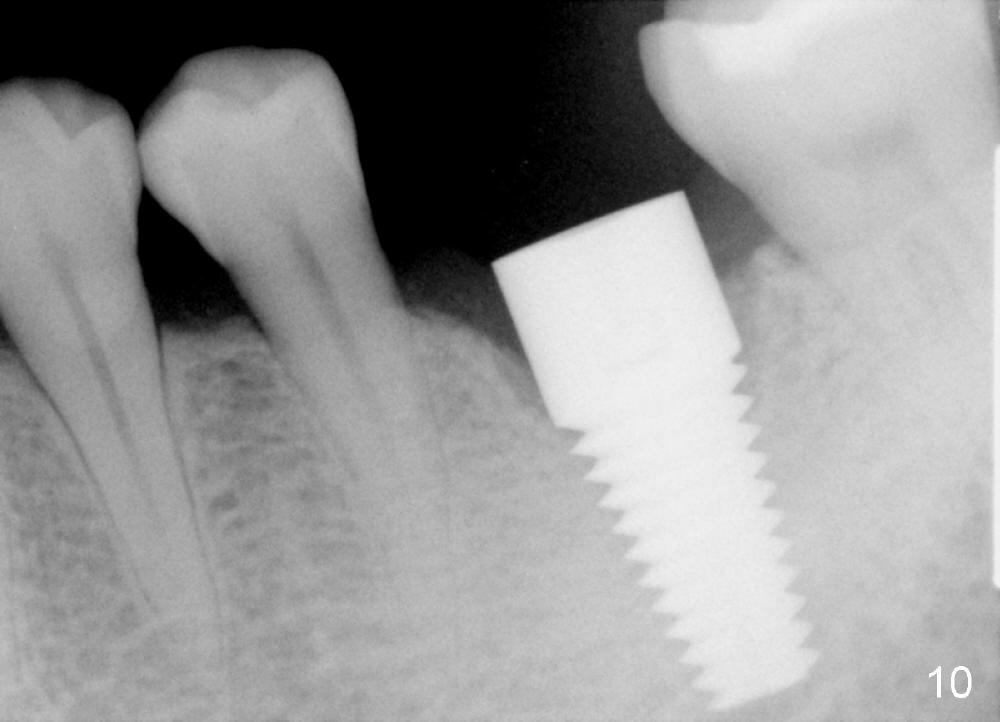

There is a thick gingival band buccal to the implant 7 months postop (Fig.9 *). Osteointegration occurs (Fig.10). The most unexpected finding is the formation of the papillae (Fig.11 *) when the permanent crown is seated. The cosmetic result is due to immediate placement of the large implant. Delayed implant usually cannot achieve this type of outcome.